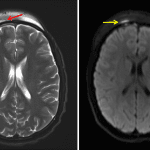

- Thin, mildly T2 hyperintense subdural collection overlying the anterior right frontal lobe with associated restricted diffusion, measuring 2 mm in thickness

- Dural thickening and enhancement along the majority of the right frontal and temporal convexities

- Complicated frontal sinusitis with subdural empyema

Acute right anterior drainage pathway sinusitis complicated by a thin right frontal convexity subdural empyema with surrounding pachymeningitis, a thin right frontal subperiosteal abscess, and right greater than left frontal scalp and periorbital cellulitis. No evidence of cerebritis or brain abscess.